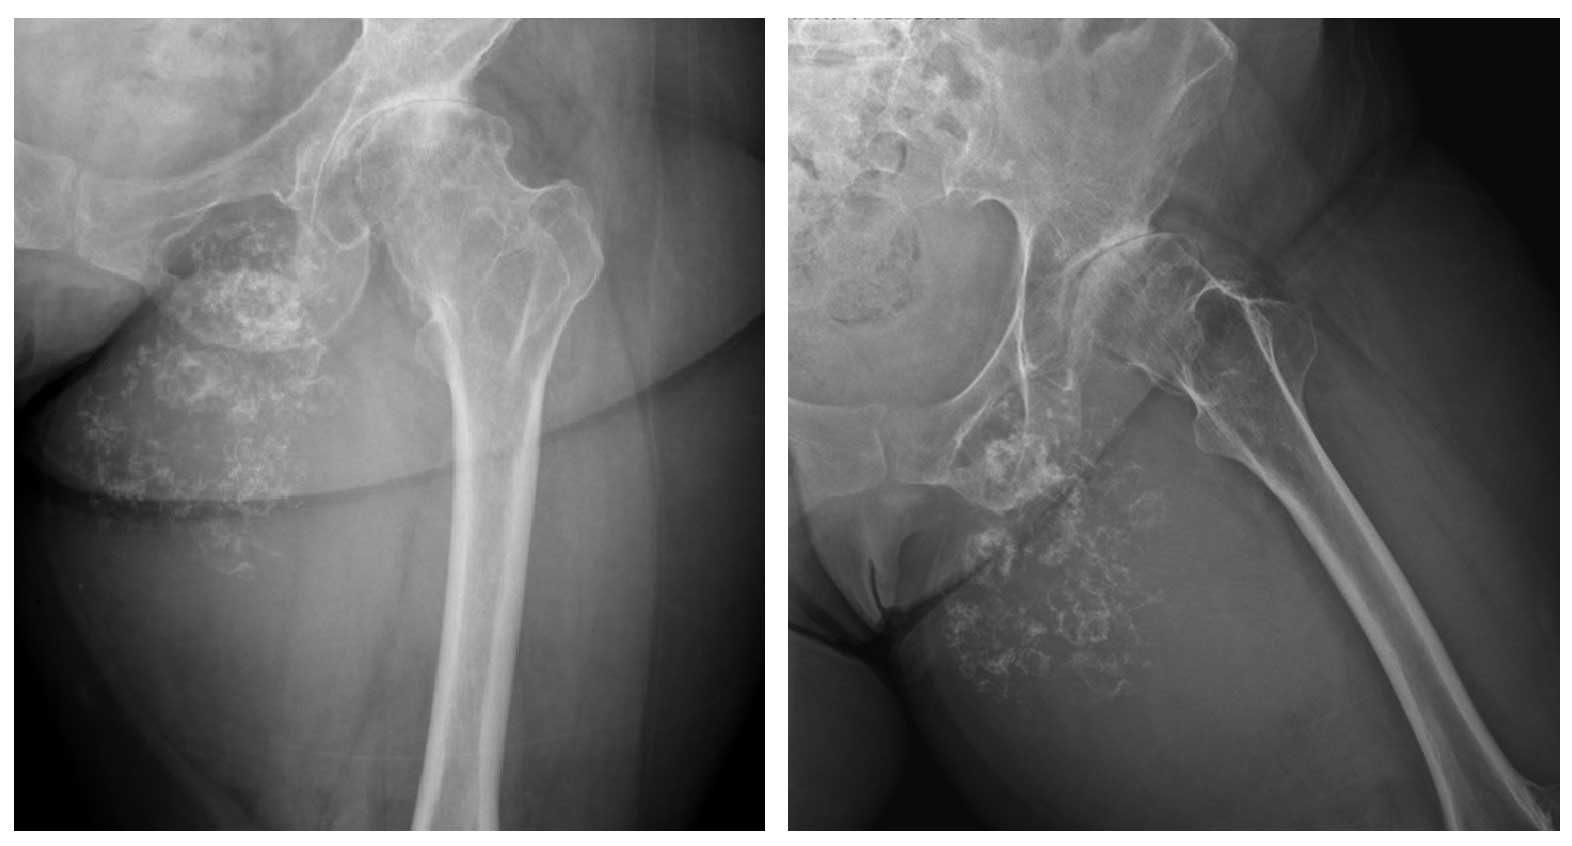

Ameliyat Öncesi: Röntgende inferior pubik kol ve astebulum alt yüzeyinden kaynaklı düzensiz kalsifikasyon içeren kitle, kalçada kireçlenme mevcutç